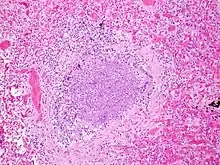

| An X-ray of a child with RSV showing the typical bilateral perihilar fullness of bronchiolitis. | |